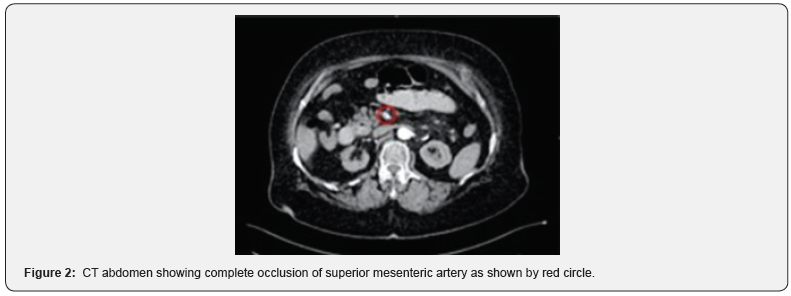

The patient initially underwent an abdominal XR (Figure 1) which displayed non-specific bowel pattern, and no abnormal air-fluid levels. Her CT Abdomen (Figure 2) revealed complete occlusion of the superior mesenteric artery, with mild dilatation of the proximal small intestinal loops showing suspicious pneumatosis intestinalis and poor post-contrast enhancement of the distal ileal loops features concerning for bowel ischemia. The patient was immediately shifted to operating theatre for midline laparotomy. There was foul-smelling serosanguinous peritoneal fluid along with complete gangrene of the small bowel, colon was healthy and other organs were unremarkable. Damage control surgery with resection of the gangrenous bowel was carried out except 30 cm distal to the duodeno-jejunal junction and 15 cm proximal to the ileocaecal valve (Figures 3 and 4).